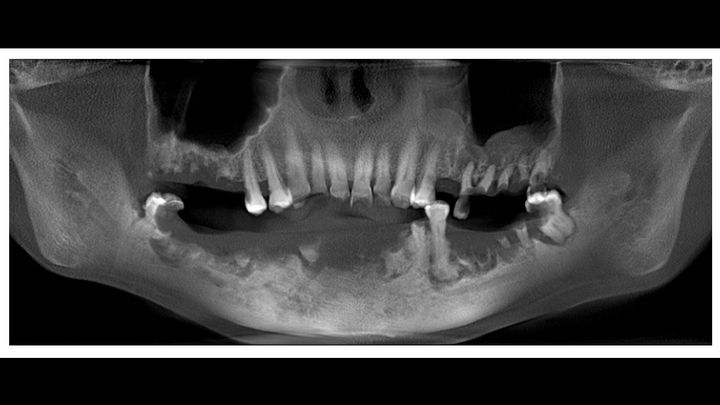

Hello! My name is Rose Maldonado. I'm 47 years old, and I'm a cancer survivor. When I just turned 26, I had cancer on my tongue. They removed almost the entire back of the right side and also extracted 47 lymph nodes. Then I received 30 sessions of radiation in the jaw and neck. I was recently diagnosed with Jaw Radiation Necrosis (JRN), a condition caused by radiation. It has destroyed all the cells and tissues of my jaw, blood does not circulate, and it has progressively expelled part of the lower teeth, It's hard for me to eat only puree and liquid, which has made me lose weight drastically, causing multiple facial inflammations, clotting, bleeding, extreme pain, fever, and severe infections. These infections put my life at great risk since they could expand to the brain, which could be fatal.